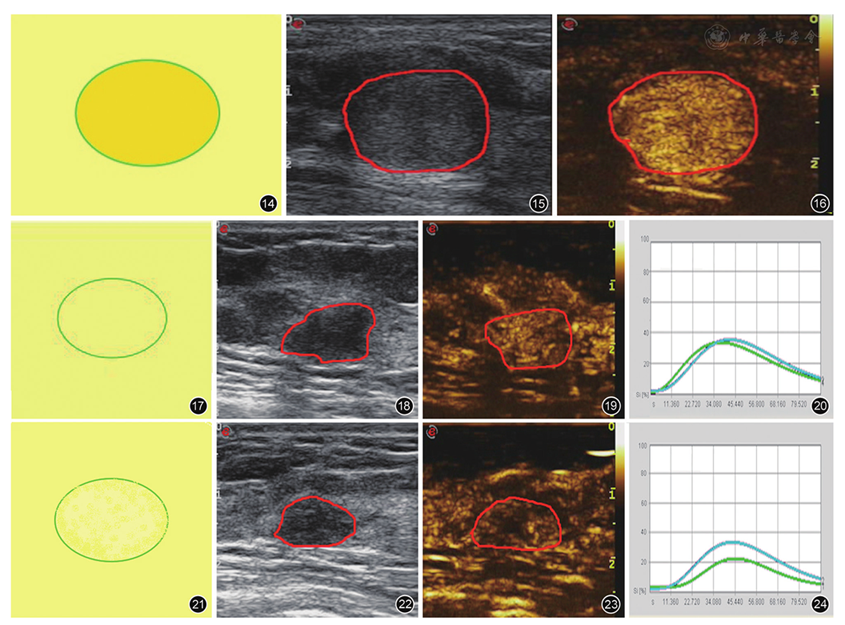

图14~24 乳腺良性病灶的超声造影预测模型。图14~16 分别为D模型示意图、二维超声表现、超声造影表现,示病灶高增强,增强后病灶大小不变,形态规则,无滋养血管;图17~19 分别为E模型示意图、二维超声表现、超声造影表现,病灶慢进或同进等增强,不能分辨病灶边界及形态,无充盈缺损和滋养血管征;图20 为E模型病灶时间-强度曲线,呈同进等增强;图21~23 分别为F模型示意图、二维超声表现、超声造影表现,病灶慢进或同进低增强,增强后大小不变或缩小,无滋养血管;图24 为F模型病灶时间-强度曲线,呈慢进低增强